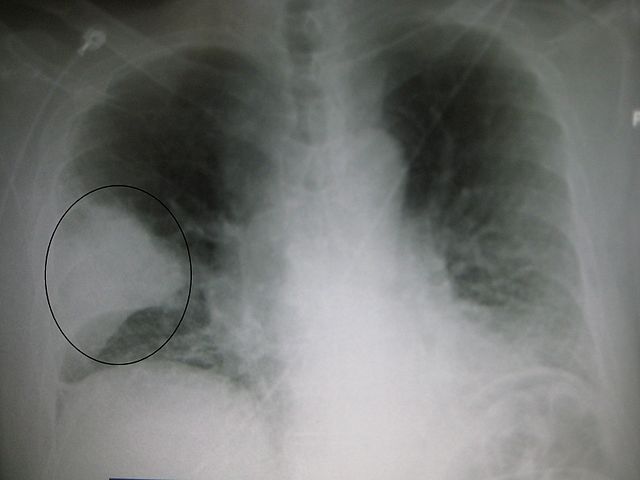

English: A very prominent pneumonia of the middle lobe of the right lung.